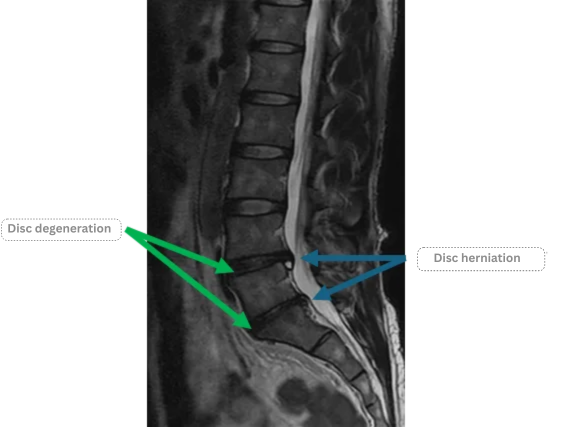

| L4/L5 | Disc degeneration, disc herniation |

| L5/S | Disc degeneration, disc herniation |

The above findings were also observed on the imaging.

The L4/L5 and L5/S intervertebral discs showed degeneration and herniation,

which are considered the most likely sources of the patient’s symptoms.